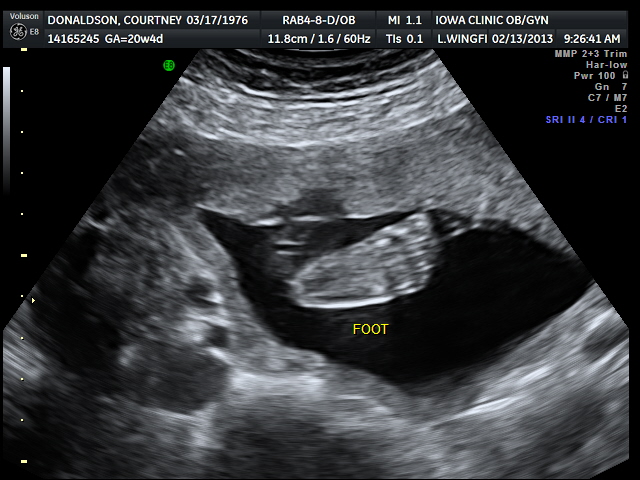

ULTRASOUND_2 February 13, 2013 by Courtney Leave a comment ← Previous Image Next Image → 20w4d – little foot Like Loading...